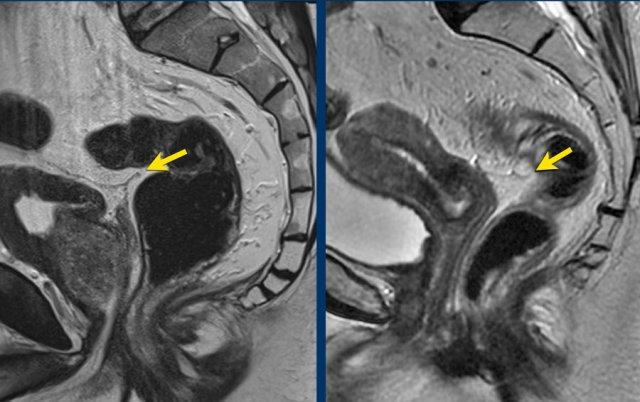

Ví dụ hình ảnh:

- Trái:Khối u nằm gần phúc mạc và bàng quang (mũi tên trắng), nhưng không xâm lấn ra ngoài lớp cơ thành ruột hoặc vào phúc mạc—không phải T4a.

- Phải:Tín hiệu khối u lan vào phúc mạc (mũi tên vàng)—xác nhận xâm lấn T4a.